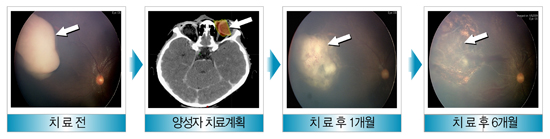

망막모세포종의 양성자 치료 사례